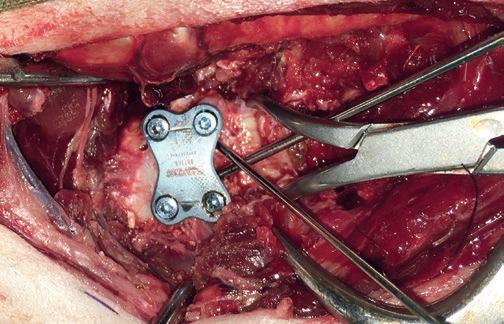

Tratamiento quirúrgico de la subluxación atlantoaxial 30

• Tratamiento quirúrgico de la subluxación atlantoaxial